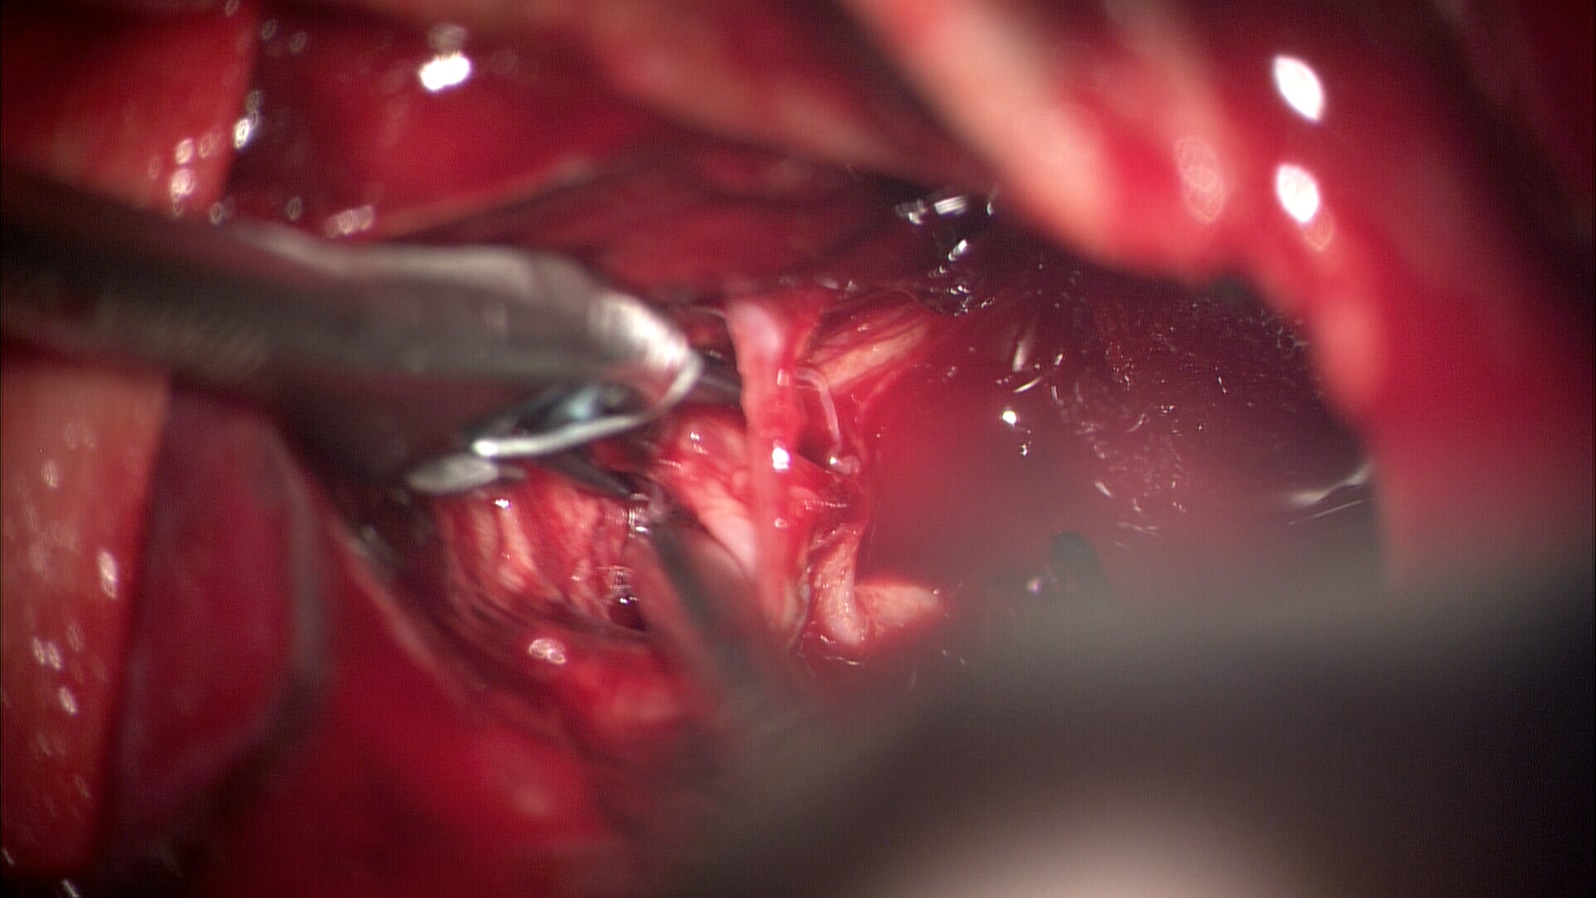

微小动脉瘤1例

患者老年女性,72岁,昏迷入院。